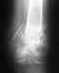

локальная деструкция лучевой кости

извините за качество снимка но основное видно локальная деструкция . Сделана ревизия в локтевой ямке до 200 мл гноя . Было ли у кого - нибудь такое в практике .фрагмент крсти околежащие ткани на исследование посланы. в анамнезе диабет тип1

• Кликните для загрузки файла 20121215_001.jpg